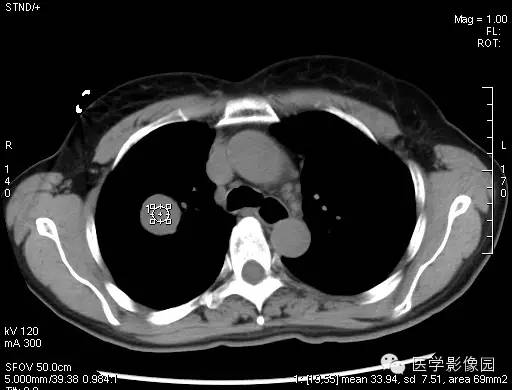

动脉期的增强在中等以上,静脉期增强在动脉期的程度上有更深程度的强化,当肿瘤边缘不清晰时,就有呈现浅分叶、胸膜凹陷、短毛刺等现象,边缘清楚、光整,多数形态规则、少数可见浅分叶,无毛刺、空洞,无卫星灶,密度均匀,偶有钙化,无胸膜凹陷征。CT增强扫描显示病灶中等以上均匀或不均匀强化,且存在延迟强化现象,对PSH具有一定的诊断价值。